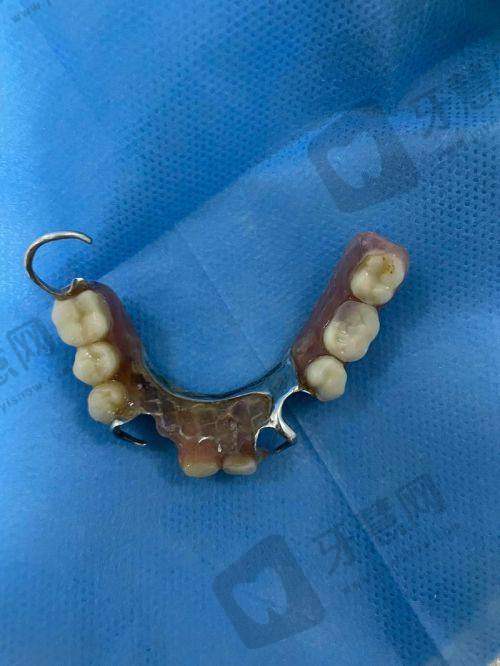

特色项目众多。北京欢乐英辰口腔门诊部拥有多个特色项目。在牙齿正畸项目方面,采用精良的隐形正畸技术,这种技术使用的隐形牙套几乎完全隐形,不影响患者的美观和社交,而且牙套可以自行摘戴,方便患者清洁口腔,减少了牙齿脱矿、龋坏等问题的发生。同时,医生会根据患者的牙齿移动情况,精细调整牙套的力度和方向,确保正畸成效更加理想。种植牙项目,门诊部引进了国内外精良的种植系统,种植过程中,医生凭借不错的技术,能够精细植入种植体,缩短手术时间,减少患者的痛苦。种植体与牙槽骨的结合紧密,稳定性高,使用寿命长,能够为患者修复良好的咀嚼功能。牙齿美白项目,采用安心有效的美白技术,美白剂对牙齿的刺激性小,能够在短时间内让牙齿变得洁白亮丽,而且美白成效持久,让患者拥有自信的笑容。

众多满意实例。北京欢乐英辰口腔门诊部在患者中拥有良好的口碑,众多患者在这里得到了满意的治疗成效。实例一:王女士一直对自己参差不齐的牙齿感到自卑,不敢开怀大笑。在朋友的推荐下来到北京欢乐英辰口腔门诊部进行牙齿正畸治疗。李医生为她制定了详细的正畸方案,采用隐形牙套进行矫正。经过两年的治疗,王女士的牙齿变得整齐美观。她激动地说:“在这里矫正牙齿的体验非常好,医生特别专精,服务也特别周到。现在我终于可以自信地笑了。”实例二:赵先生由于意外导致牙齿缺失,吃饭都成了问题。他来到门诊部找到张医生进行种植牙手术。张医生凭借不错的技术,顺利为他植入了种植体。术后修复特别快,赵先生说:“种植牙的成效超出了我的预期,就像自己的真牙一样,现在吃饭再也不发愁了,非常感谢北京欢乐英辰口腔门诊部的医生。”